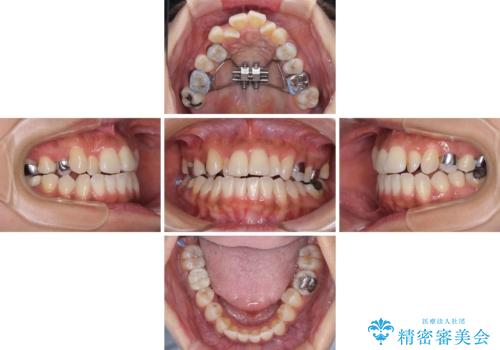

【モニター】幅の狭い上顎歯列 骨幅を拡大する矯正治療

- 上の歯の歯並びを気にして来院された患者様です。

上顎骨の横幅が狭く、歯列が混み合っていたため、急速拡大装置により側方拡大し、咬み合わせと歯列を改善することとしました。

下顎は部分的に咬み合わせに問題があったため、部分的な装置を付けることとしました。

骨格的な問題を解決したことで、下顎は部分矯正で対応することができました。